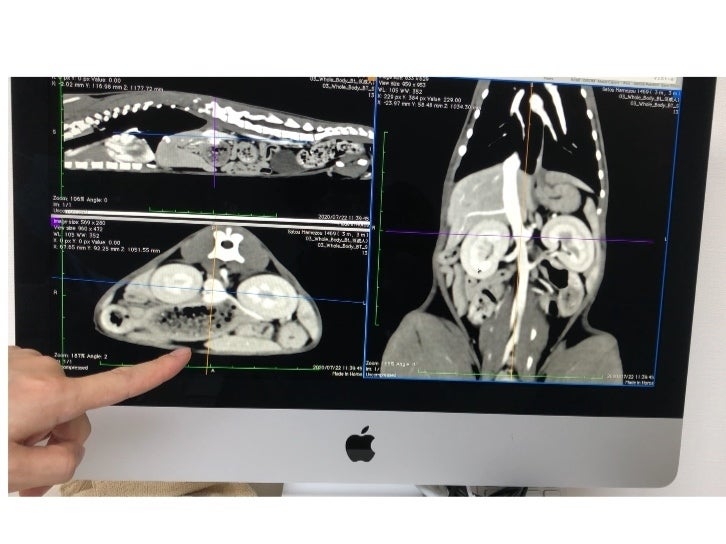

それでも食欲は旺盛で、毎日短時間ですがはしゃいでいる姿はとても可愛くて、手術をできる状態にもっていけるように預かりBABAさんが毎日の投薬に励み、ようやく先日CTスキャンによる検査を受けてきました。

画像診断の結果は、門脈シャントと確定したものの、門脈が異様に細い為かなり難易度が高い手術だということで、1度の手術では対応出来ず、最低でも2回、もしくは3回に分けて手術をしなければならず、1回目の手術代の目安は約20万円、2回目の手術と術前のCT検査で20万円、3回目は15万円ととても高額な目安になると言われました。